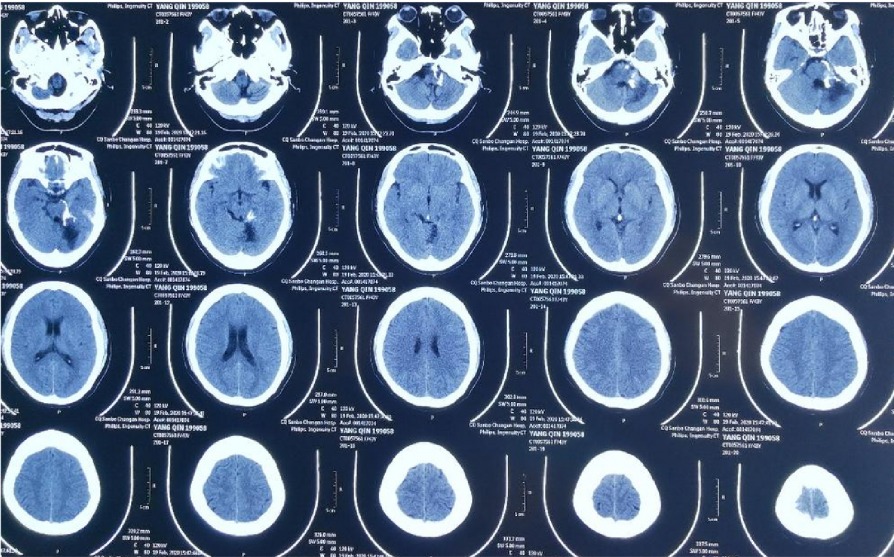

CTA 结果

MR显⽰桥脑左侧⾼信号影

小脑及脑⼲受累

本次⼊院⾏DSA检查:PICA供⾎区有畸形⾎管团,引流到横窦